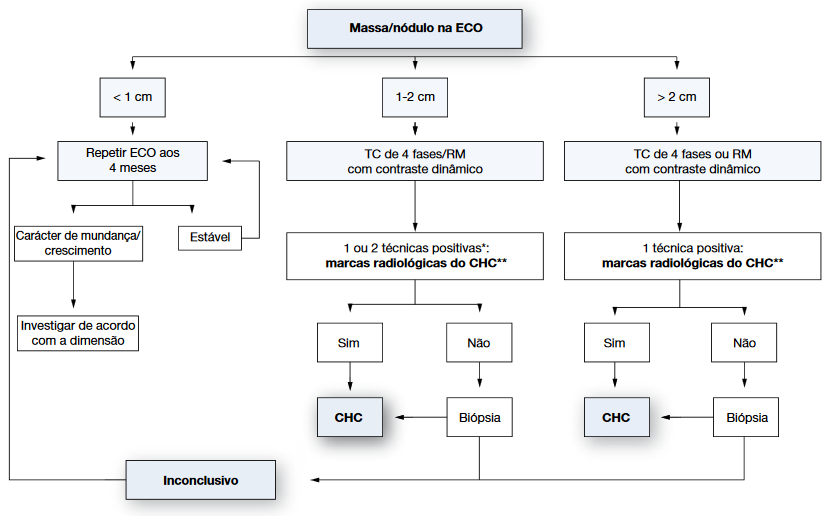

Como ocorre na grande maioria das vezes em uma população bem definida, os portadores de cirrose, é de fundamental importância que essas pessoas sejam acompanhadas rotineiramente por um especialista habituado ao diagnóstico deste tipo de câncer ainda em suas fases iniciais. O método mais recomendado para isso é a ultrassonografia abdominal periódica (geralmente semestral), realizada por médico experiente, acompanhada ou não da dosagem de alfa fetoproteína no sangue.

Uma vez diagnosticada a lesão, a presença de dois exames de imagem (geralmente tomografia computadorizada e ressonância nuclear magnética) com achados típicos é considerada suficiente para o diagnóstico, não sendo necessária a realização de biópsia na maioria dos casos.